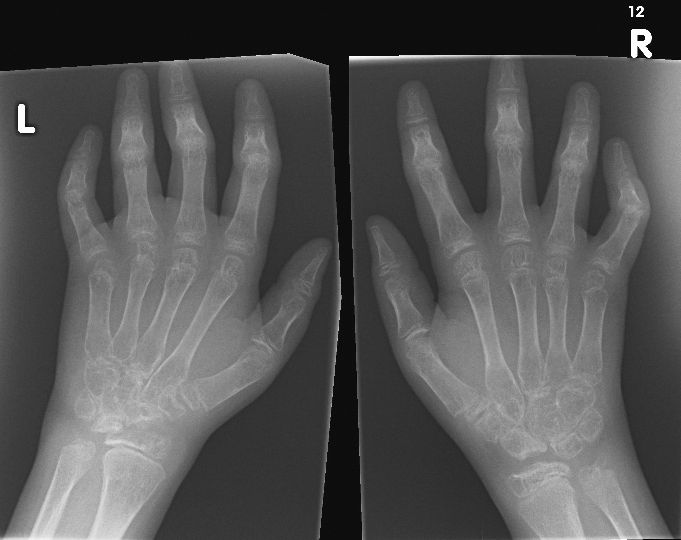

Image IQ Quiz: Child Presents With Joint Pain, Swelling

What is the diagnosis in this child?

Patient presents with joint pain and swelling. What is the diagnosis?